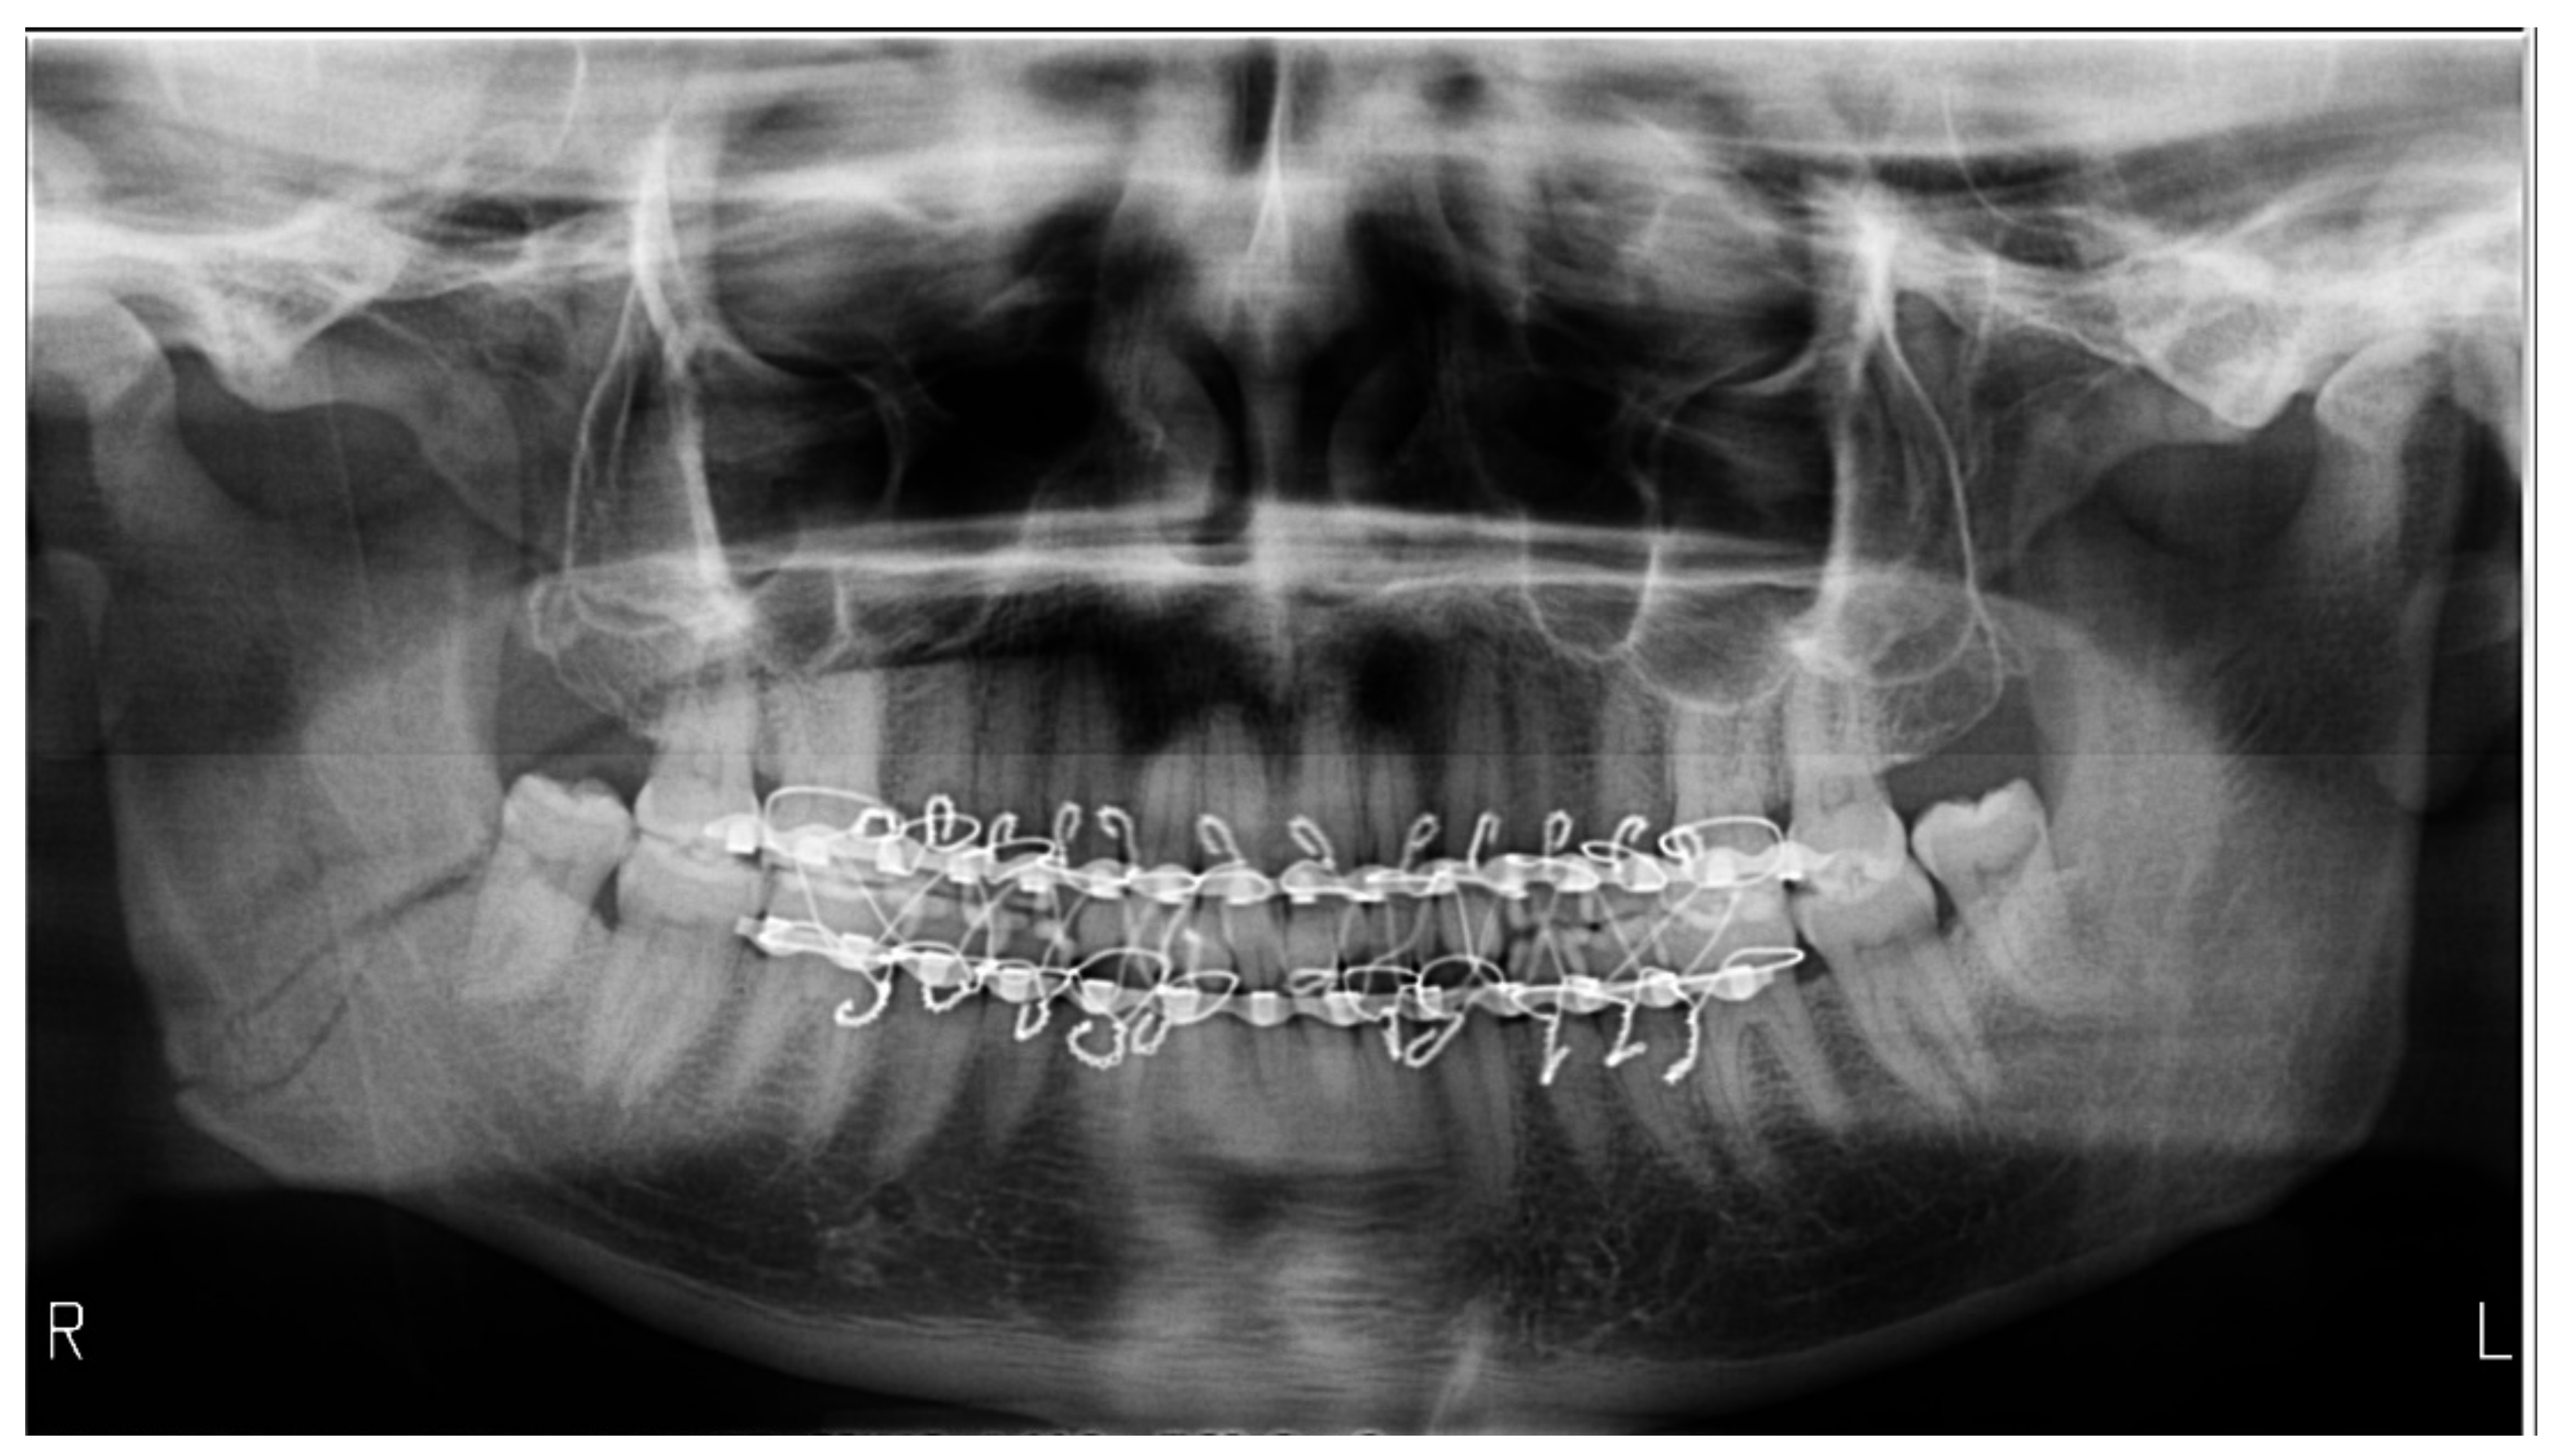

Dislocated Jaw X Ray

Learning Radiology - Dislocated, Mandible, Mandibular, Dislocation Dislocated Jaw: Symptoms and Treatment Bilateral temporomandibular joint dislocation | Radiology Case ... Pretreatment X-ray showing the anterior dislocation. | Download ... Learning Radiology - Dislocated, Mandible, Mandibular, Dislocation Dislocated Jaw X Ray